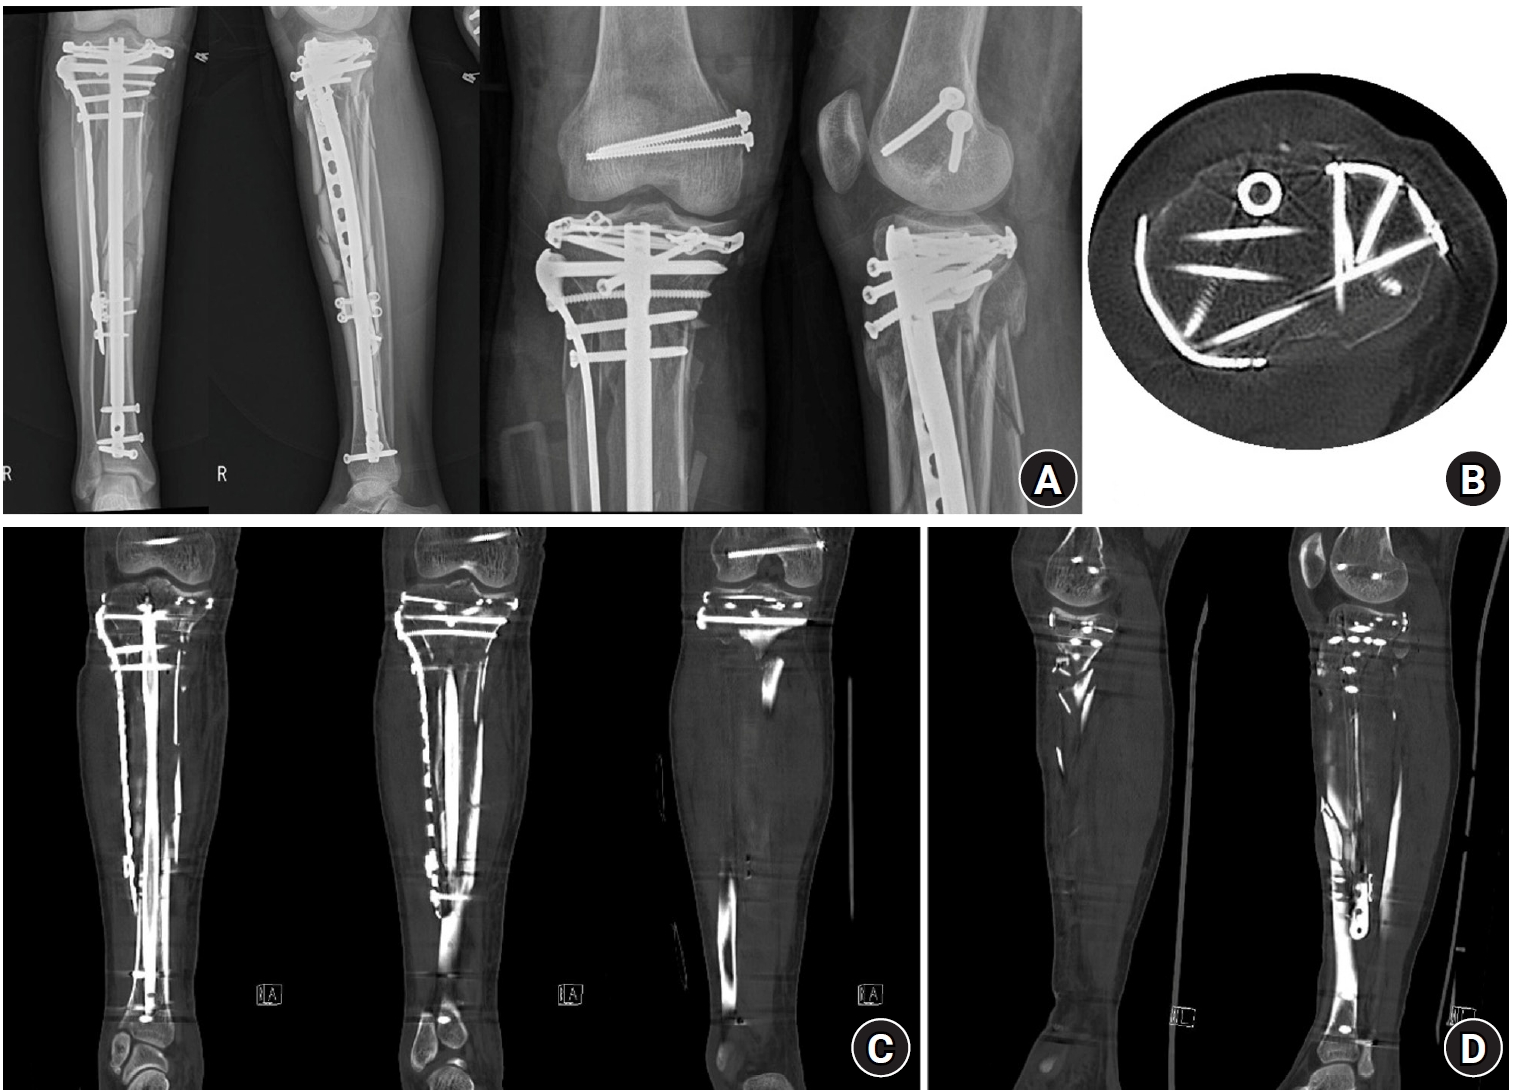

Fig. 3.

Postoperative plain radiographs and computed tomography (CT) images. (A) Postoperative plain radiograph. (B) Axial CT image confirming that screws from the rim plate did not interfere with the intramedullary nail trajectory. (C) Coronal CT image after fixation. (D) Sagittal CT image after fixation.

jmt-2025-00290f3.jpg